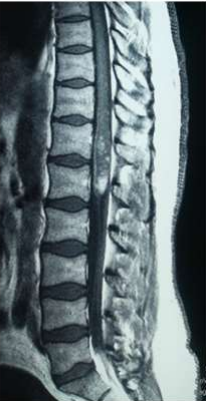

Image (7) Sagittal MRI of the Case No (5) Showing cord expansion at the level of conus medullaris with absence of subdural space and some hyperintense patches

Image (8) Sagittal MRI of the Case No (7) Showing cord expansion at the level of conus medullaris with absence of subdural space and some hyperintense patches.

Eight of the ten patients were diagnosed utilizing MRI which showed Dorsal 12 to Lumber 1 or 2 spinal cord swelling with hyper intense patches in T2 images , while the remaining two patient were diagnosed utilizing CT myelogram which showed Dorsal 12 to Lumber 1 or 2 spinal cord swelling.

Magnetic resonance imaging in spinal schistosomiasis usually shows swollen conus and epiconus beside areas of hyper-signal in T2 and heterogeneous contrast enhancement[12]. Multinodular intramedullary contrast enhancement of the distal cord allowed accurate preoperative MR imaging diagnosis of spinal schistosomiasis[12]. Cerebrospinal fluid (CSF) may show changes in spinal schistosomiasis. Characteristic features are mild to moderate pleocytosis, presence of eosinophils, slight to moderate protein increase, elevated gamma globulin concentration and a positive immune assay. These abnormalities are not always, accidentally schistosomal ovae may appear in the cerebrospinal fluid [13].